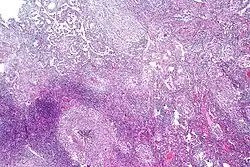

Pulmonary tuberculosis characterized by granulomatous inflammation with necrotizing epithelioid granulomas. Low power view. H&E stain.

Pulmonary tuberculosis characterized by granulomatous inflammation with necrotizing epithelioid granulomas. Low power view. H&E stain. -